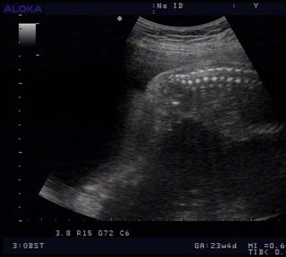

宝宝B超图